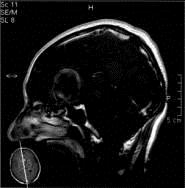

问题 病历摘要:??患者男性,56岁,因右侧视力下降伴视野缺损2个月来院就诊,诉头痛,无明显头晕,无视物重影,无恶心呕吐,无肢体抽搐,无肢体乏力,胃纳佳,大小便正常,既往史无特殊,入院检查:神志清楚,言语清楚,体毛分布正常,左侧视力4.6,右侧视力4.0,粗侧右颞侧视野缺损,左侧正常,颈软,四肢肌张力正常,肌力正常,病理征(-)。 结合影像学,考虑诊断为??提示:入院检查内分泌激素正常,为明确诊断,检查头部?MRI,如右图所示。

选项 A.鞍结节脑膜瘤 B.垂体腺瘤 C.颅咽管瘤 D.动脉瘤 E.胆脂瘤 F.异位松果体瘤

答案 D